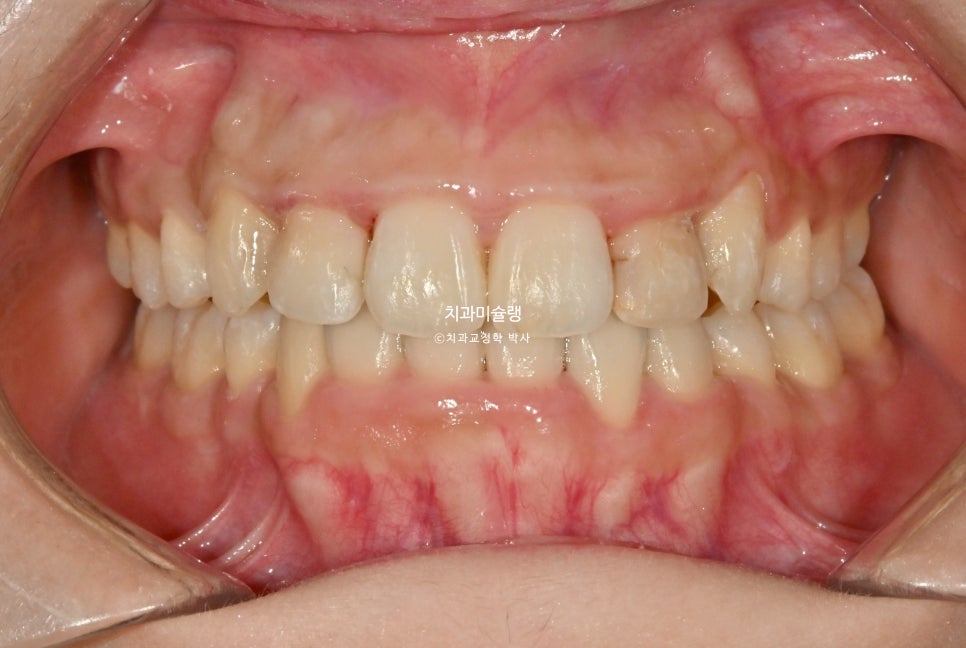

2026년 2월 – 치료 완료

약 한달간 마지막 30번 장치를 밤에만 끼면서 어금니 교합 안정화를 도모한후 26년 2월, 드디어 치료를 마무리 합니다.

중심선은 잘 맞으며 송곳니 덧니는 예쁘게 배열되었습니다.

잇몸이 치아를 과하게 많이 덮고 있는 만큼 블랙트라이앵글 없이 마무리 되었습니다.

어금니 교합은 1급 교합관계를 달성, 한달간의 합 안정화를 통해 물샐틈 없는 교합이 되었습니다.

악궁형태나 배열이 이상적입니다.

총 치료기간은 2년 4개월, 재제작은 1회 했습니다.